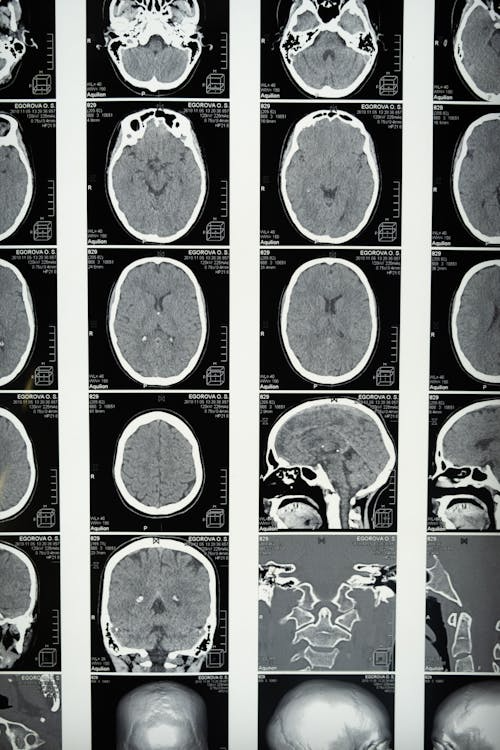

3️⃣ CT/MRI 검사 – 뇌부종이나 합병증 여부를 확인하기 위해 시행됩니다.